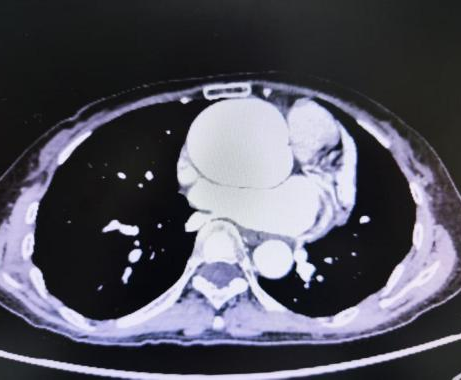

心脏彩超和主动脉 CTA 检查明确诊断为:升主动脉瘤样扩张(最宽处直径约 6.0 厘米)+ 主动脉瓣重度关闭不全。 经详细询问病史及详细体格检查,张阿姨还被诊断为「马凡综合症」且有家族遗传现象。

「正常升主动脉直径一般不超过 4 厘米,现在张阿姨的血管已经扩张到最宽 6 厘米,就像被吹胀的气球,壁薄得不堪重负。」

胸心血管外科石磊副主任医师解释,当升主动脉直径扩张 ≥ 4.5 厘米或直径超过正常部位的 1.5 倍以上时可形成动脉瘤,血管壁难以承重,随时可能引发主动脉夹层或破裂,死亡率极高,堪称 「埋在胸膛里的不定时炸弹」。